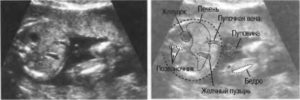

Желудок на УЗИ определяется как округлое или овальное анэхогенное образование, расположенное в верхнелевых отделах полости живота. Изменения с его стороны могут быть признаками патологии желудочно-кишечного тракта или косвенными признаками других неблагоприятных состояний.

На УЗИ в 20 недель желудок у плода имеет округлую или овальную форму анэхогенного образования с жидким содержимым. Расположен в верхнем квадранте животика. Размеры зависят от количества заглатываемых околоплодных вод.

Определить аномалии развитие желудка у плода возможно только по УЗИ. Изображение на аппарате позволяет определить объем, размеры органа в динамике и в реальном времени уже с 20 недели.